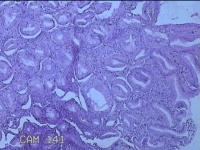

胃窦粘膜

女

30岁

慢性胃炎;胃食管反流

上腹部疼痛1周余。

灰白粉红色组织小米大一团。

片子这个效果,诊断起来比较困难。